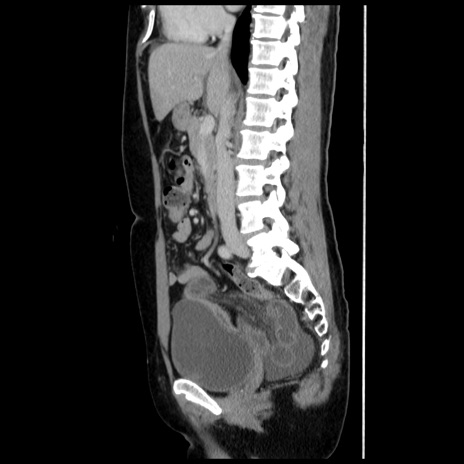

症例10(矢状断像)

【症例】 50歳代女性

【主訴】 腹痛

【現病歴】前日生レバーを食べた。今朝に排便あり。 昼前に突然発症の腹痛を生じ、当院救急外来を受診した。

【既往歴】 子宮筋腫にてで子宮全摘後

【身体所見】 意識清明、腹部:平坦、軟、下腹部やや左を中心に圧痛・反跳痛あり、筋性防御あり

【データ】WBC 7800、CRP 0.07